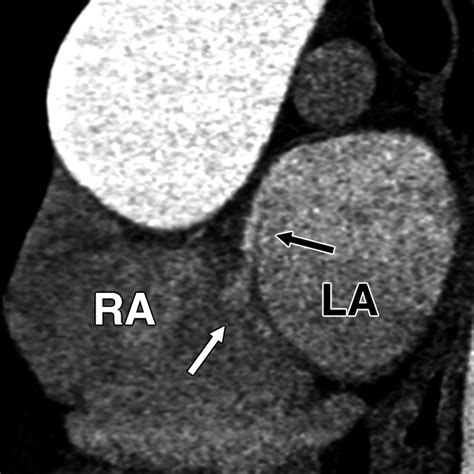

• Echocardiogram: This is a non-invasive test that uses sound waves to create images of the heart. A transesophageal echocardiogram (TEE) is often used to get a clearer view of the heart's structures.

• Bubble Study: During an echocardiogram, a saline solution with microbubbles is injected into a vein. If the bubbles appear in the left atrium, it indicates the presence of a PFO.

• CT Scan: A computed tomography scan can provide detailed images of the heart and help identify a PFO.